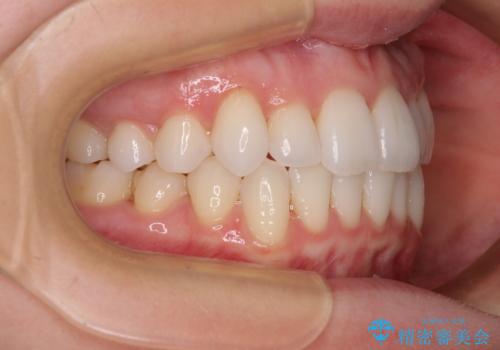

- 上下前歯のデコボコ、特に右上の八重歯を気にして来院された患者様です。

妊娠、出産の予定があり、毎月の通院が困難となる可能性があったため、インビザラインによる矯正治療を行うこととしました。

事前に親知らずを抜歯しておき、出産時期に困ることのないように準備をした上で治療を開始しました。

治療後半では悪阻によりマウスピースの装着時間が不十分となることもありましたが、それよりも前にしっかりと装着時間を守って治療を進めることができたため、特に気になるところなく治療を終えることができました。